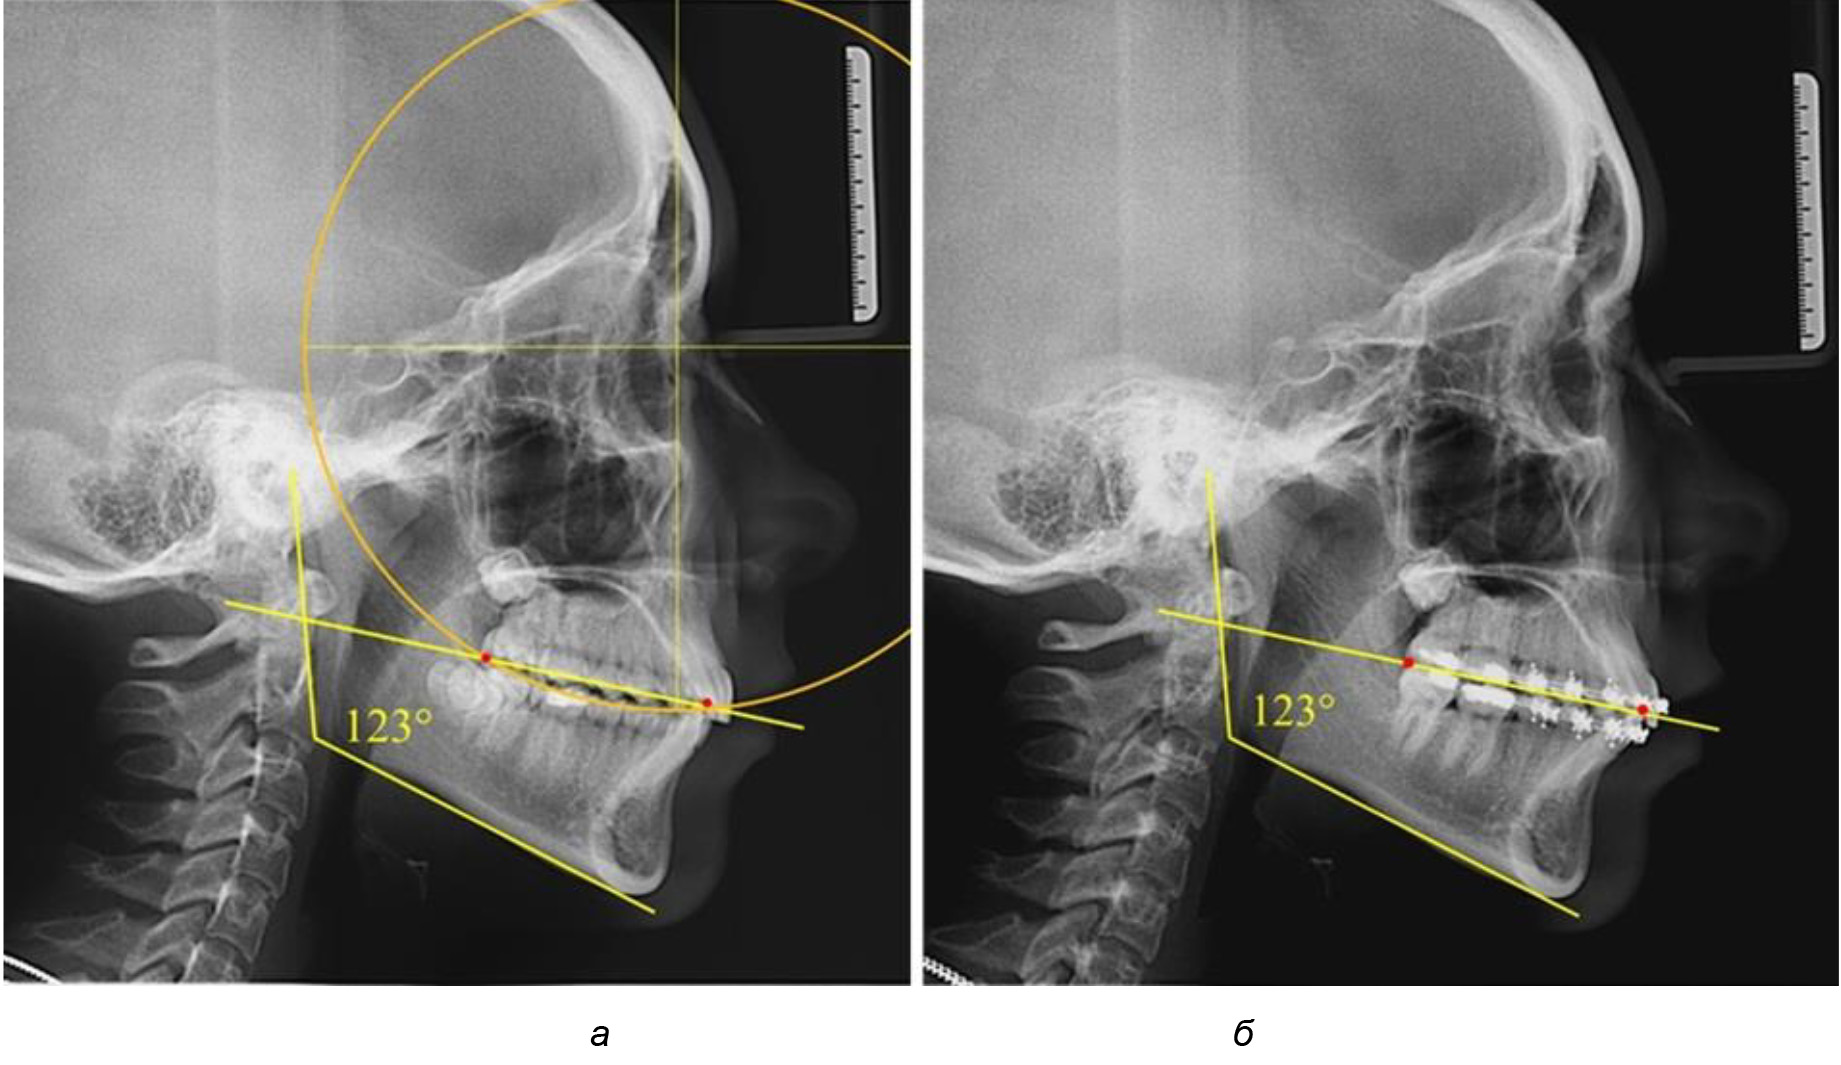

У людей с аномалиями окклюзии по сагиттали в 1-й подгруппе обследовано 9 человек. Обращает на себя внимание увеличение глубины кривой Spee, что нами расценивалось, как патологическая форма кривой линии окклюзии.

Глубина кривой Spee в среднем по 2-й подгруппе составила (5,69 ± 1,57) мм, что было достоверно больше, чем у людей с физиологической окклюзией (р ˂ 0,05). Достоверных различий с показателями, полученными при анализе ТРГ и ОПТГ, нами не отмечено (р ˃ 0,05). Отношение радиуса окружности к сагиттальному размеру окклюзионной линии в среднем по подгруппе составляло 1,372 ± 0,042 и не соответствовало числу Фибоначчи, что может быть использовано в качестве диагностического критерия определения патологической формы кривой Spee. После лечения пациентов техникой «прямой» дуги было отмечено незначительное увеличение сагиттального размера окклюзионной лини в среднем на (2,12 ± 0,77) мм. Однако окклюзионная линия практически касалась окклюзионного контура всех жевательных зубов, и отмечалось практически полное отсутствие кривой Spee.

Таким образом, проведенное лечение техникой «прямой» дуги способствует нормализации окклюзионного равновесия и торку передних зубов, однако не соответствует оптимальному окклюзионному статусу, характеризующему физиологическую окклюзию. При этом величина нижнечелюстного угла оставалась на прежнем уровне (рис. 5).

Рис. 5. Особенности ТРГ при патологической кривой Spee до лечения (а) и после лечения (б) техникой «прямой» дуги